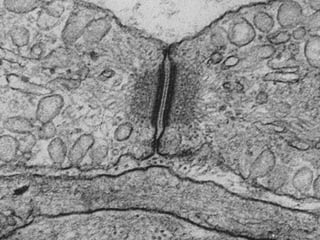

Este documento presenta imágenes microscópicas de diferentes tipos de tejidos y estructuras celulares teñidas con varios métodos histológicos. Incluye fotografías que muestran fibras de colágeno, elásticas y reticulares en diversos órganos, así como membranas basales y células especializadas de órganos como riñones, glándulas mamarias y próstata. El propósito es demostrar la aplicación de técnicas histológicas para visualizar componentes celulares y tej